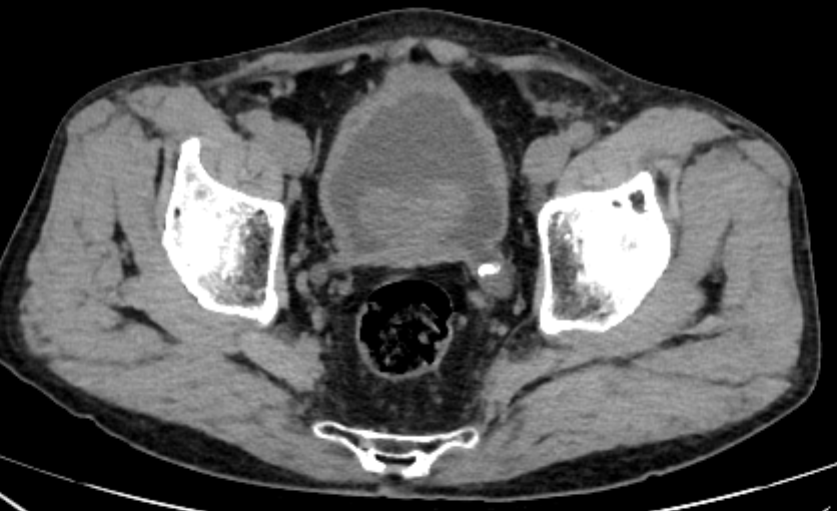

李新教授为彭大爷完善 CTU 检查后,考虑患者诊断:1. 重度前列腺增生;2. 膀胱多发结石;3. 双侧输尿管扩张伴双肾积水;4. 梗阻性肾衰竭。

彭大爷腰痛的原因,是前列腺增生致排尿困难进而导致双上尿路积水所致,外院所述「输尿管结石」应为膀胱憩室内多发结石,患者腰痛系由增生的前列腺压迫输尿管开口所致。

李新教授与泌尿外科团队进行了详尽的术前讨论,考虑患者目前主要问题为前列腺重度增生,完善术前准备后,为彭大爷安排全麻下行经尿道前列腺电切术+膀胱结石钬激光碎石取石术。

李新教授手术中仔细操作,在前列腺电切过程中仔细辨认输尿管开口,避免输尿管损伤,手术过程顺利,术中发现膀胱多发憩室,憩室可见数枚结石,术后诊断与术前诊断吻合,术后患者恢复良好。